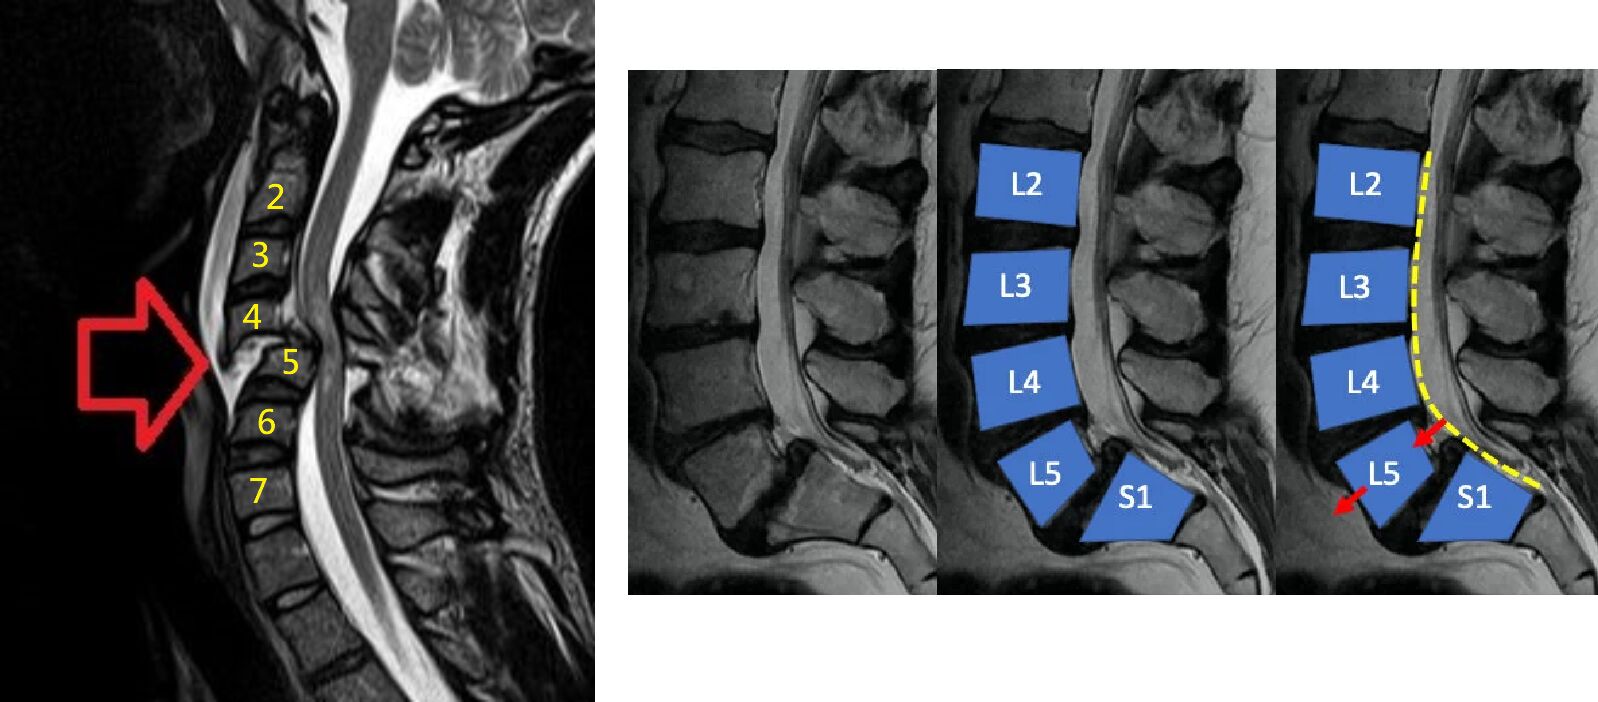

(A) 影像顯示為頸椎第四節C5滑脫(spondylolisthesis),導致第四脊髓壓迫損傷

標上頸椎節數,脫離正常曲線的是C5,且這並非滑脫,滑脫在影像上應該是椎體前移(謝謝社群丁丁提醒)

whiplash會造成前髓或中髓受損,但前髓症候群是只有後柱徑本體覺保留,其餘都受損

「上肢力氣比下肢差,感覺有保留」,是中髓症候群